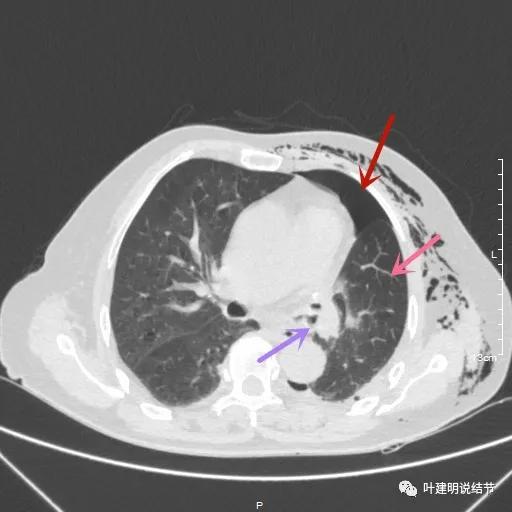

术后第二天患者乏力纳差,起不了床!而且CRP也大于100,我们的神经又紧张起来,怕支气管胸膜瘘,怕感染、怕有并发症发生。还好化验后是低钾,予以补充钾与镁2天后胃纳与精神均有明显改善,我们再加用静脉高营养支持治疗,补充白蛋白,情况逐渐好转。我们也于术后第4天查了CT,发现如下:

下叶膨胀良好

下叶膨胀良好,上叶残腔不大

下叶膨胀良好,上叶残腔不大,蓝色箭头示左主支气管

下叶膨胀良好,上叶残腔不大。桔色箭头示吻合口处,通畅

以上图像示下叶膨胀良好,上叶残腔不大,紫色箭头示吻合口以远的支气管通畅,肺膨胀佳